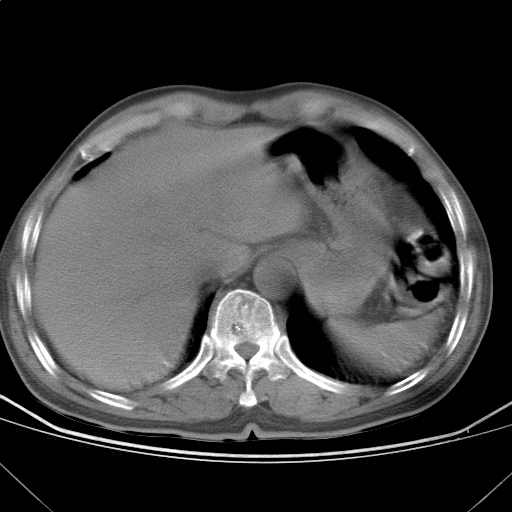

以下是引用随光逐影在2009-5-1 13:53:00的发言:[br]考虑为:1)两肺血行播散型肺结核;2)右肺下叶炎症感染。3)右侧胸膜增厚。